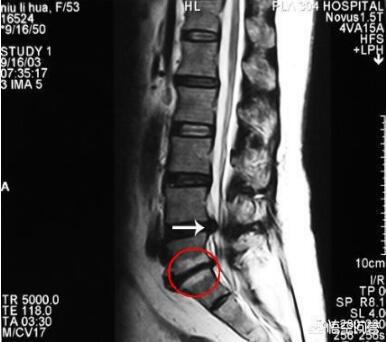

如果我猜的没错的话,你应该是做的腰椎间盘CT,在报告中这么写的,一般描述是椎间盘内可见气体密度影,在影像学上也叫椎间盘内真空征。

这是由于椎间盘内髓核脱水和变性,使髓核内积气的真空现象。椎间盘内气体的存在是一种变性征象,不表示出现这个就一定会发生腰椎间盘突出,当然也是可以同时发生腰椎间盘突出的!

不过出现这个影像,应该讲脊柱的退变是比较严重的,椎间盘的功能要变差,随之可能会出现椎间隙变窄,关节突关节退变等问题。